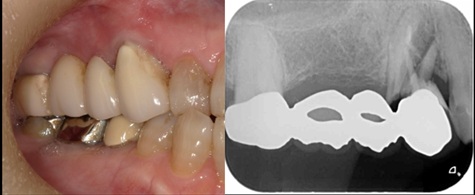

下顎管まで近いケースショートインプラントと垂直GBR(骨造成)で対応した →インプラント埋入

治療前

治療後

施術名 | インプラント埋入垂直GBR(骨造成) |

主訴 | 噛めない |

施術の副作用(リスク) | 感染脱落 |

施術の価格 | 1本GBR5万~10万(税抜き)+インプラント埋入補綴まで35万(税抜き) FGG5万 |

コメント | 下顎管まで近いケースショートインプラントと垂直GBR(骨造成)を同時に行いました |